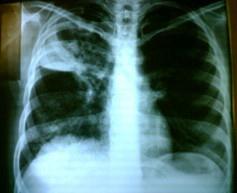

问题 男,55岁,有肺结核史,近1个月来咳嗽、低热,痰中带血,X线胸片如图所示: 为确诊采取哪种检查方法最佳 ( )

选项 A、痰找瘤细胞,放射性核素扫描 B、胸部CT检查,支气管镜检查 C、胸部CT检查,经胸壁穿刺活检 D、支气管镜检查,纵隔镜检查 E、痰找抗酸杆菌,痰找瘤细胞

答案 B